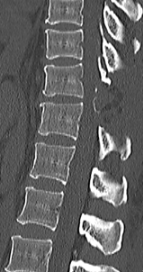

胸椎黄色靱帯骨化症を認め脊髄を圧迫している状態です。骨化部分を切除することで脊髄の圧迫を解除し症状は改善しています。